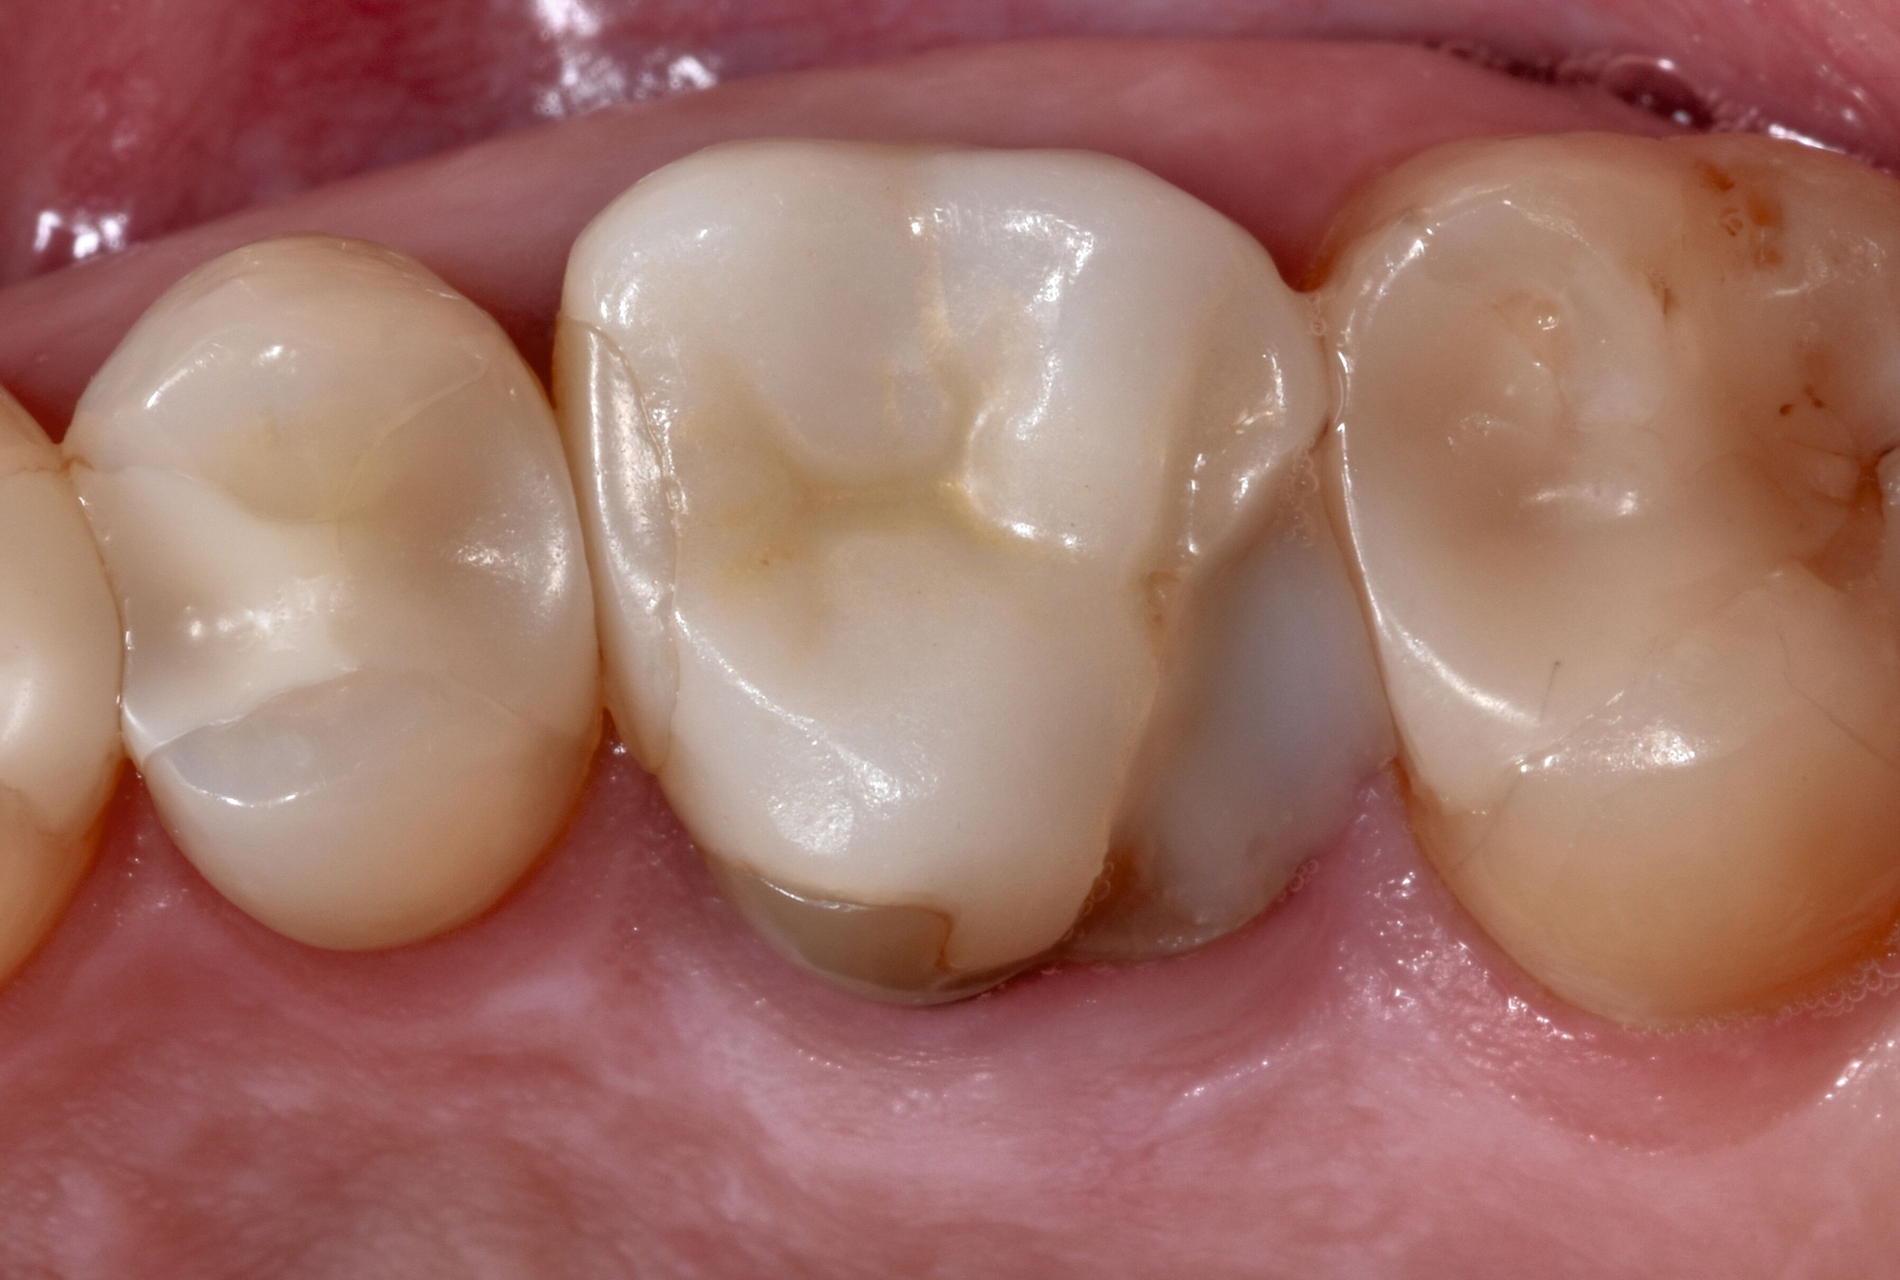

Nach Anwendung eines Universaladhäsivs und Lichtpolymerisation wird die Kastenelevation mithilfe der „Schneepflug-Technik“ eingebracht: Zunächst wird mit einer zahnärztlichen Sonde eine kleine Menge Flow-Komposit auf die Kavität aufgebracht, aber keine Lichthärtung vorgenommen. In das weiche, ungehärtete Flow-Komposit wird visköses Restaurations-Komposit einmodelliert und die approximale Stufe im distalen Bereich des Zahnes auf ein supragingivales Niveau angehoben.

Der Effekt durch die Vermischung der beiden Kompositmaterialien in ungehärtetem Zustand besteht in der Optimierung der marginalen Adaptation und der Verbesserung der Randqualität am subgingivalen Bereich. Nach Abnahme der Matrize erfolgt eine erneute Lichtpolymerisation und die Ausarbeitung der subgingivalen Restaurationsränder mithilfe eines sichelförmigen Skalpells (Nr. 12), von Finierdiamanten und gegebenenfalls von oszillierenden diamantierten Shape-Feilen (Abbildung 2).